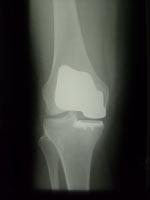

• Verschleiß der Gelenkflächen kann zu einer schmerzhaften Einsteifung, Fehlstellung oder Instabilität des Kniegelenkes führen. Moderne Prothesen ersetzen ein, zwei oder alle drei Gelenkanteile (die Innenseite, die Kniescheibe und ihr Gleitlager, die Außenseite). Die Prothesenteile sind ungekoppelt oder – bei Vorliegen einer Instabilität – achsgeführt und zumeist zementiert.

Zweidrittelprothese Zweidrittelprothese Oberflächenprothese Oberflächenprothese